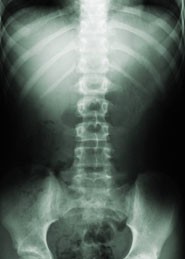

Researchers are one step closer to understanding how an individual's genetic make-up predisposes them to Ankylosing Spondylitis (AS), a common auto-immune arthritis which causes pain and stiffness of the spine, and in serious cases, progressive fusion of the vertebrae and other affected joints. The study is published today. The team of researchers from the Universities of Bristol, Queensland (Australia), Oxford, Texas and Toronto, used a technique called genome-wide association where millions of genetic markers are measured in thousands of people that have the disease and thousands of healthy individuals. Markers which are more frequent in individuals with the disease are more likely to be involved in the condition. Using this approach the investigators found an additional seven genes likely to be involved in the condition, bringing the total number of genes known to predispose to AS to thirteen. Many of the new genes are already known to be involved in inflammatory and immune processes, providing researchers with further clues about how the disease arises. Two of the new genes are also known to predispose to other auto-immune conditions including Crohn's disease (a form of inflammatory bowel disease) and Celiac disease (an auto-immune intestinal disease).